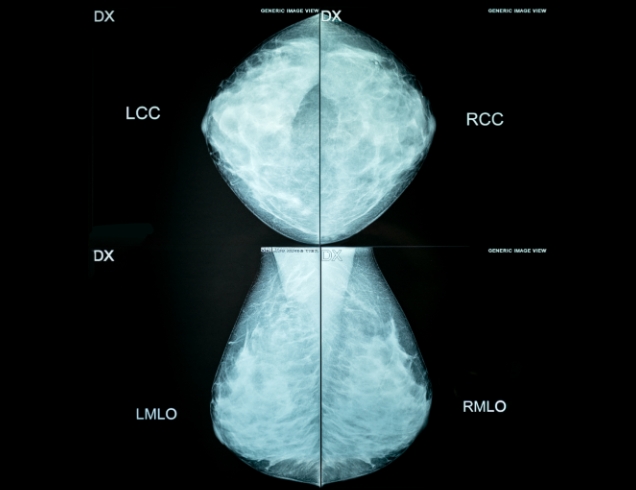

유방암 검사

고해상도 초음파 기기를 이용하여 유방 질환을 진단하는 검사입니다.

유방암 검사 대상

유방에 멍울이 만져지는 여성

유두 분비 증상이 있는 여성

정기적인 유방암 검사 대상자

진단 질병

유방암

유방의 양성혹 (섬유선종)

물혹 (낭종)

농양